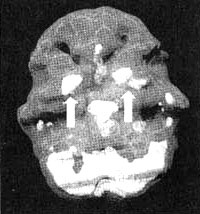

Система базальных ганглиев

Трехмерное изображение — активный мозг, вид сбоку.

Трехмерное изображение — активный мозг, вид снизу.

Базальные ганглии — это комплекс крупных образований, расположенных в центральной части мозга окружающих центральную лимбическую систему.

Базальные ганглии участвуют в процессах интегрирования чувств, мыслей и движений, а также в регулировании моторной функции. Базальные ганглии задают наше у организму режим, а котором он работает а состоянии покоя или уровень тревожности. Кроме того, они способствуют модулированию мотивации и, по всей вероятности, отдают за ощущения удовольствия и экстаза. Рассмотрим каждую из этих функций более подробно.